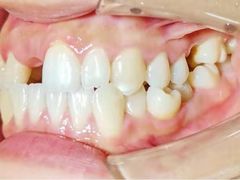

• -联合口腔(西环诊所)

在丽江古城跳舞的炒鸡蛋 | 21-05-08

报错